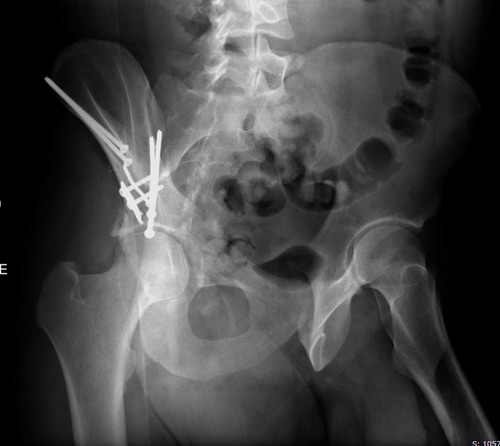

Нами подобные повреждения были неоднократно излечены при помощи аппаратного остеосинтеза на базе Илизаровского. Используется концепция отдельно управляемых стержней и аппарат модификации Г.И. Лобанова. Интересные решения для впадины были помнится мне и у Рункова А.В.

Кроме того, всегда во время репозиции и фиксации аппаратом можно сделать ограниченный доступ в проекции илиоингвинального по типу рабочих "окон" для контроля положения отломков мануально. Да и ЭОП вам в помощь)))

Наложив аппарат, вы как минимум ничего не потеряете, больной станет мобильным, и может быть при необходимости транспортирован куда угодно.

Добрый день уважаемые коллеги. При отсутствии погружных конструкций, аппаратное лечение можно рассматривать как выход из ситуации.Только я бы не стал пользоваться стержнями и закрыто пытаться в аппарате выполнять репозицию. предлагаю как вариант: подвздошный доступ, под визуальным контролем выполнить репозицию, и не выходить на сустав, площадь фрактурной поверхности очень большая, все свежее, встанет все на место, фиксацию выполнить пучком спиц( 5-7 бедренных спиц) как и стержни мы вводим в крылья, только чтобы все спицы со стороны повреждения проходили через перелом. Положение спиц проконтролировать под ЭОпом. И смонтировать такую же переднюю раму( только спицевую). вариант думаю имеет место жить. Сразу уточню, достаточно стабильно( сам делал в качестве первичной фиксации, при более тяжелых повреждениях) А оптимально конечно ORIF.

Всем привет!!! Высокий неполный перелом передней колонны, на 3 вертлужных проекциях предполагаю конгруэнтность не нарушена (предполагаю). Под контролем эопа можно сдавить крылья, если положение улучшается - закрыто спицы трансфрактурно с формированием аппарата - передняя рама из г образных спиц. Со стороны повреждения обязательно часть трансфрактурных (после репозиции), если нарушена конгруэнтность - открытый маневр - подвздошый доступ с фиксацией тем же аппратом. Если не получилось - отправляйте в центр (убрать спицы и повторить маневр с внутренними фиксаторами не проблема... С уважением РАВ.

Представленные слайды Александром из Севастополя, имеет ценность, но, кроме inlet, остальные стандартные Judet рентген снимки должны показать правоту принятого решения. Возможно, здесь фиксация перелома вертлужной впадины, но по рентгену трудно понять!

Здесь пример перелома передней стенки, где сохранен принцип фиксации передней колонны. Для доступа Smith Petersen с остеотомией ASIS. Мышца сарториус отодвинута, и сделана ре-фиксация на свое место винтами. При хорошем обзоре, наличие Farabeuf или Jungblud forceps облегчит репозицию.